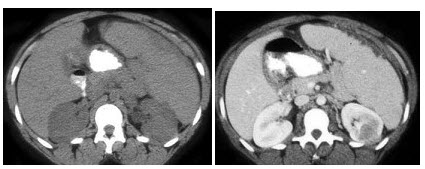

26、多项选择题

男,55岁,尿频,尿痛伴低热乏力1月。如图所示,下列说法正确的是()

A.左侧输尿管多发性狭窄

B.右侧肾积水

C.膀胱变形

D.左侧输尿管结核

E.左侧输尿管癌